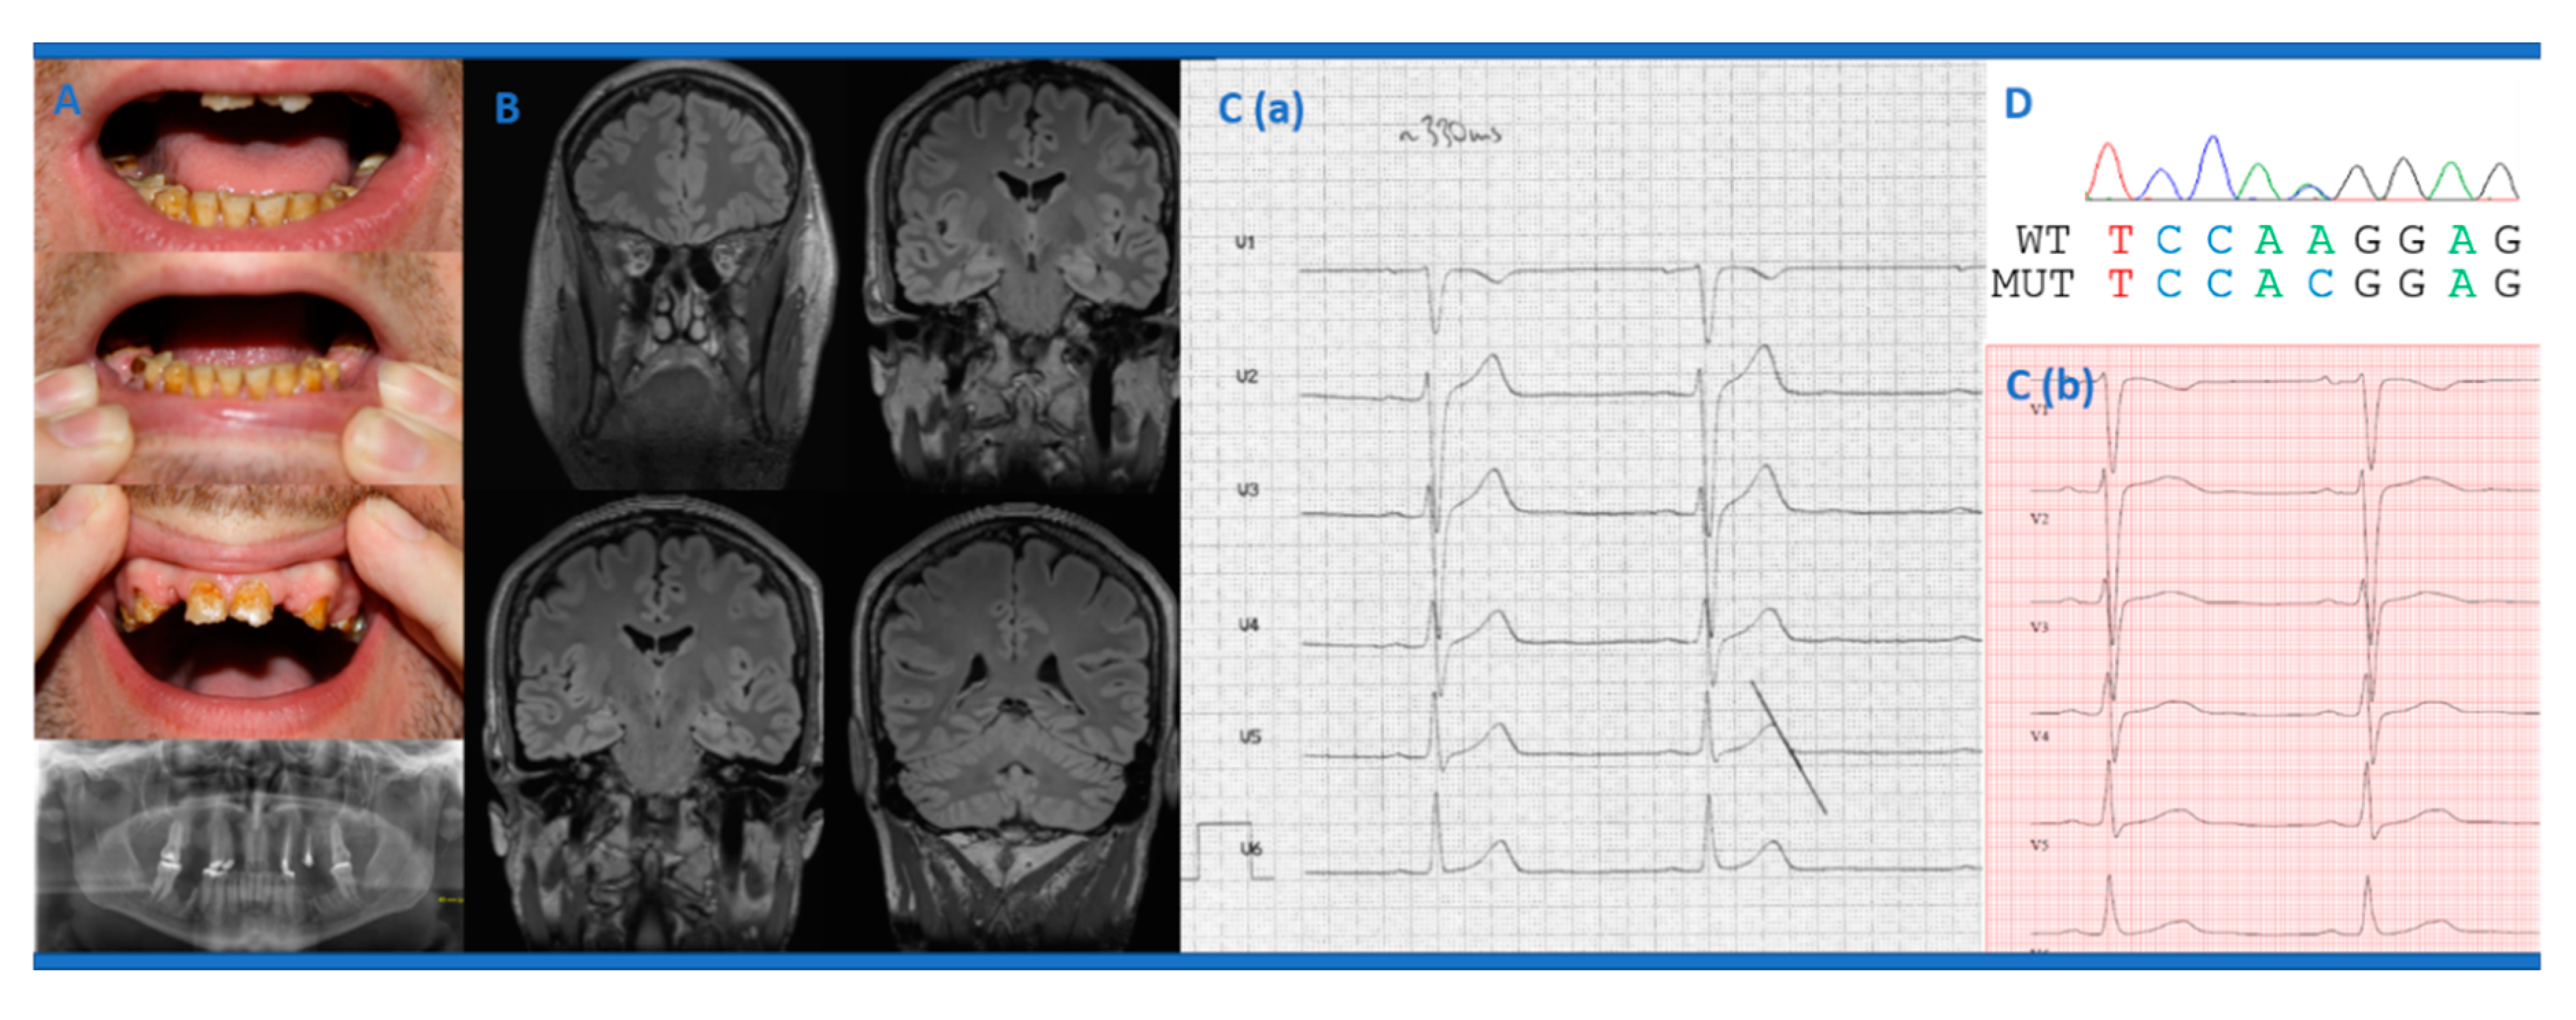

New Cav1.2 Channelopathy with High-Functioning Autism, Affective Disorder, Severe Dental Enamel Defects, a Short QT Interval, and a Novel CACNA1C Loss-of-Function Mutation

2. Case Presentation

2.1. Clinical Case Description

2.2. Genetic Analyses

2.3. Electrophysiological Analyses